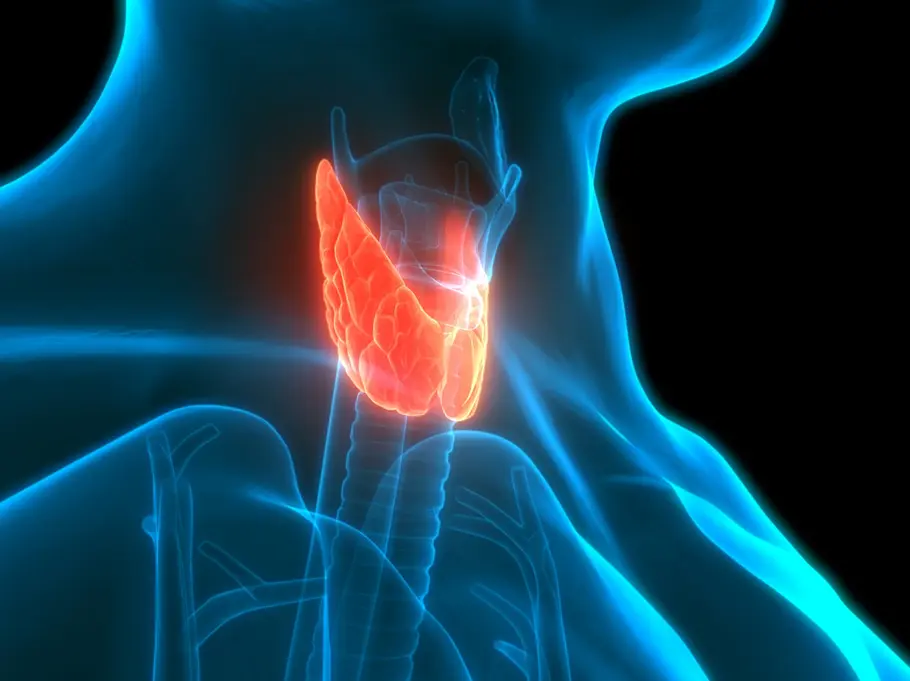

Jodmangel: Problematisch für die Schilddrüse

In deinem Körper wird das Spurenelement Jod zu fast ausschließlich zur Herstellung der Schilddrüsenhormone benötigt – also zur richtigen Funktion der Schilddrüse. Unter die genannten Schilddrüsenhormone fallen zum Beispiel Thyroxin und Trijodthyronin.

Wird also zu wenig Jod aufgenommen, kann die Schilddrüse nicht richtig funktionieren. Welche Jodmangel-Symptome weisen auf den Mangel am Nährstoff hin?